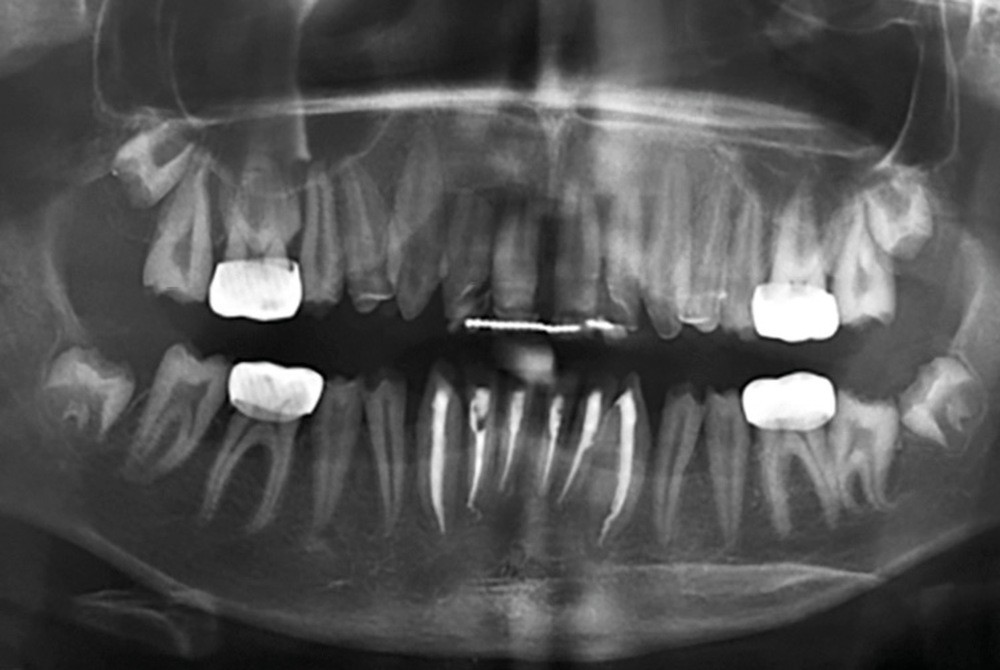

Une patiente âgée de 12 ans a été adressée au cabinet pour « une prise en charge complète sur le long terme » par son praticien traitant. Elle était accompagnée par sa mère. Elle présentait des couronnes transitoires en résine sur le secteur incisivo-canin au maxillaire ainsi que les premières prémolaires, des coiffes pédodontiques métalliques sur les premières molaires, une absence totale d’émail sur l’ensemble de la denture, à l’exclusion des bords libres des incisives mandibulaires (fig. 1 à 3). Le bloc incisivo-canin mandibulaire avait bénéficié de traitements radiculaires (fig. 4). Les incisives maxillaires présentaient des rhizalyses d’une importance significative (fig. 5 et 6). La patiente se plaignait d’hypersensibilités à la mastication et au brossage, la demande esthétique était forte.

Elle présentait une classe II division I associant une proalvéolie incisive supérieure à une rétromandibulie.